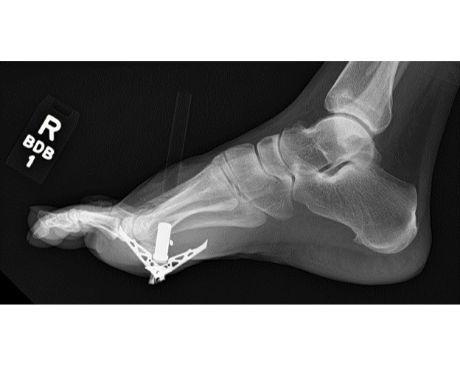

I was hit by car, had a compound fracture with a bone sticking out of my left foot. Broken tibia and fibia?. Screwed plate and bones back together. I am healing fine, next visit 3/26 to remove stiches. I seem to have total function of foot. Still have 2 more weeks of not using leg, but very hopeful.